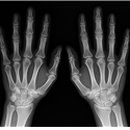

올바른 청구 G6501 수골 1매 × 1회 ※ 착오청구 예시 • G6502 수골 2매 × 1회 • G6501 수골 1매 × 2회 Q2... 올바른 청구 G6502 수골 2매 × 1회 ※ 착오청구 예시 • G6501 수골 1매 × 4회 • G6504 수골 4매 × 1회 • G6502...

올바른청구 G6502 수골 2 매 × 1 회 G6501 수골 1 매 × 2 회 G6501 수골 1 매 × 1 회 건강보험 요양급여비용... 1 매 5,400 6,170 G6502 나 . 2 매 7,650 8,730 G6503 다 . 3 매 8,990 10,260 G6504 라 . 4 매 10,330 11,780 G6505 마 . 5 매...

다-165 수골 Hand G6501 가. 1매 G6502 나. 2매 G6503 다. 3매 G6504 라. 4매 G6505 마. 5매 또는 그 이상 6. 다-166 수근골 Carpal Bone G6601 가. 1매 G6602 나. 2매 G6603 다. 3매 G6604 라. 4매 G6605 마. 5매 또는 그 이상

의료행위 건수를 부풀려 거짓청구 □□□의원의 경우, ‘손목의 상세불명 부분의 염좌 및 긴장(S6359)’ 등의 상병으로 내원한 수급권자 ○○○은 실제 수골 2매(G6502)를 촬영하였으나, 청구 시에는 수골 3매...